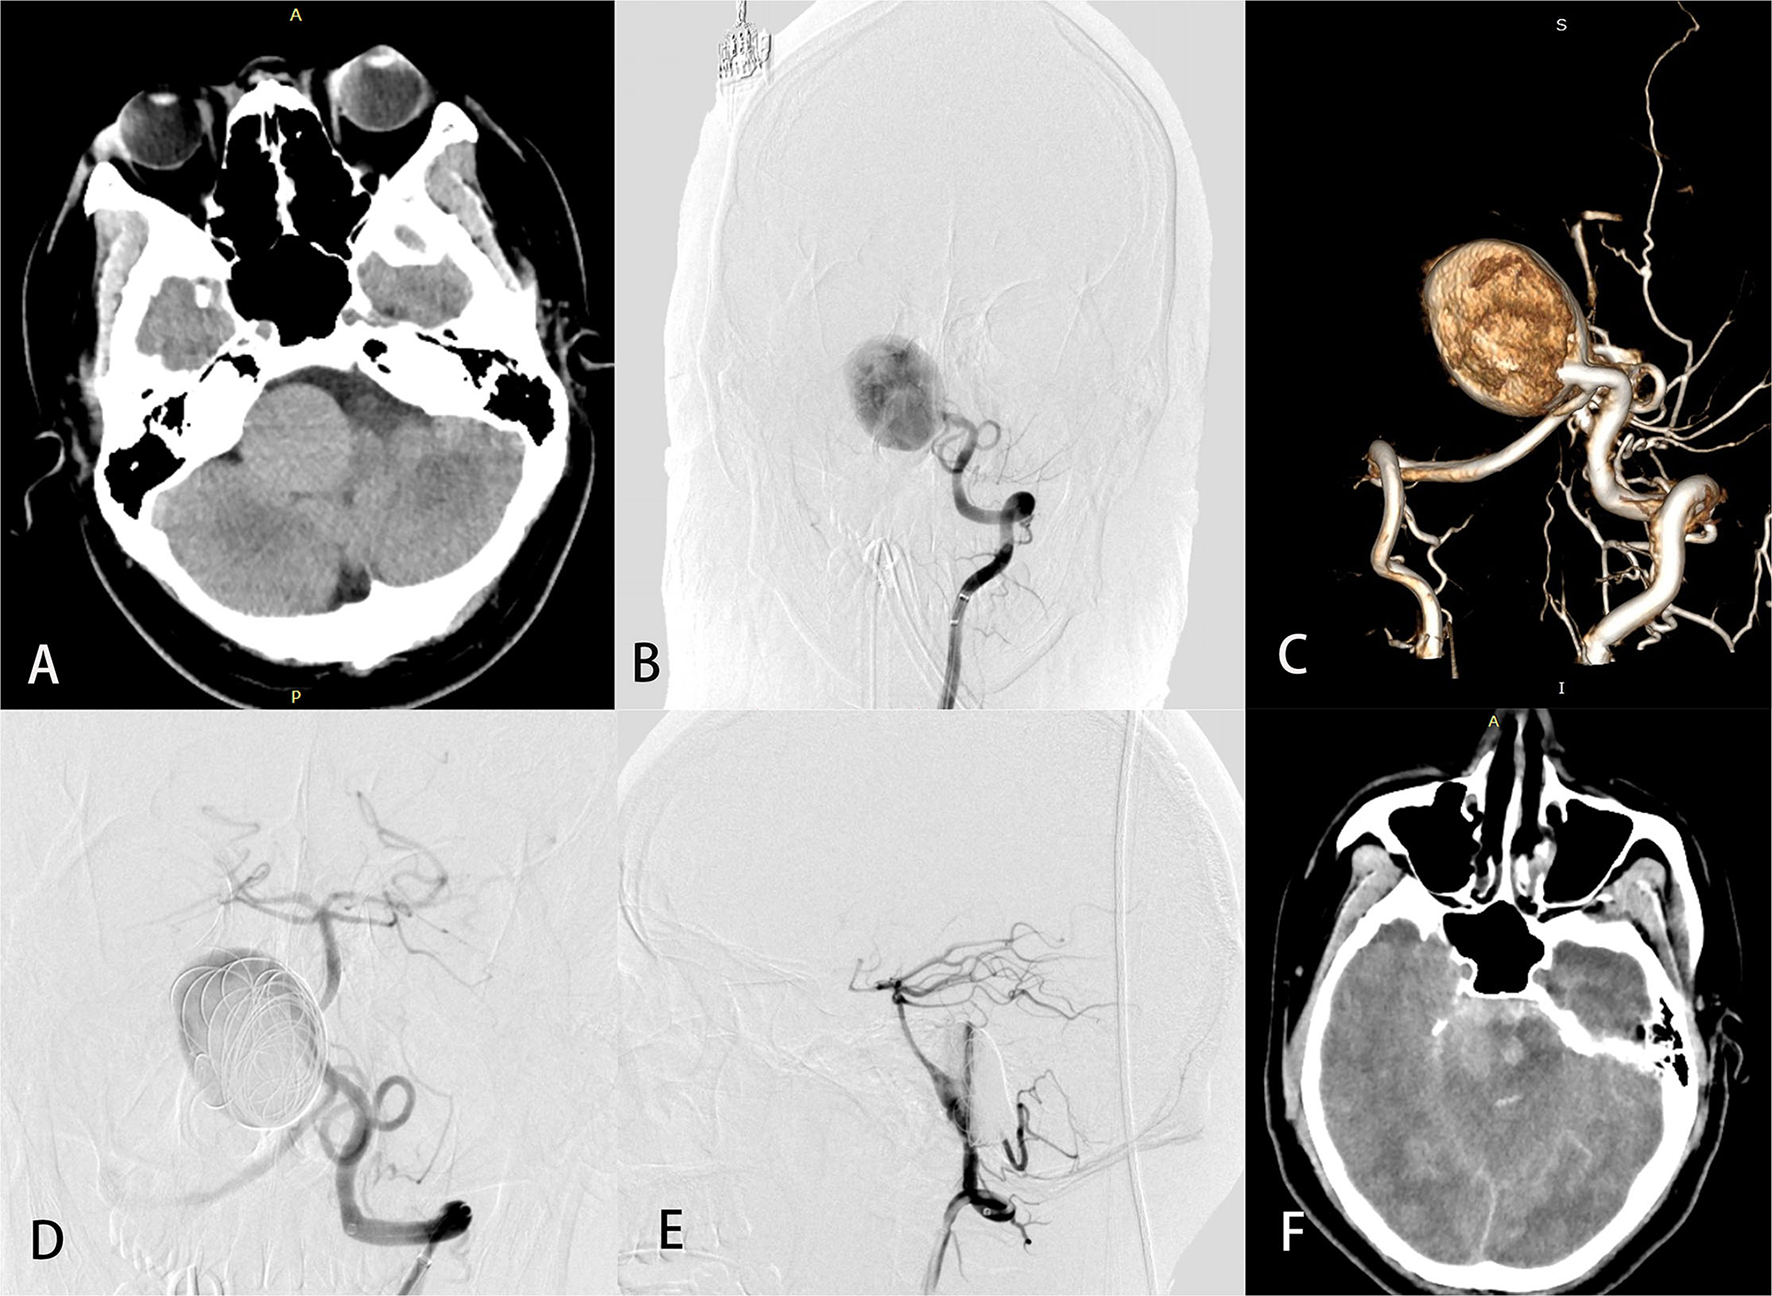

In the perioperative period, four patients with aneurysm size ranging from 22 to 40 mm developed fatal subarachnoid hemorrhage. Three of the four SAHs occurred in patients with aneurysms located on the proximal segment of the BA, including two with a VBJ aneurysm who underwent placement of a single PED without coiling and contralateral vertebral sacrifice. Figure 3 demonstrates an illustrative case (case 29).

Figure 3

A 26-year-old man (case 29) with a giant basilar artery aneurysm presented with tinnitus. Preoperative computed tomography (A) showed a large mass in the right anterior brainstem. Preoperative angiography (B) with 3-dimensional reconstruction (C) showed a giant side wall saccular aneurysm of the proximal basilar artery. Anteroposterior (D) and lateral (E) views of left vertebral angiography demonstrated excellent reconstruction of the basilar artery and contrast stasis in the lumen of the aneurysm. Computed tomography (F) on postprocedure day 3 was obtained to evaluate headache, vomiting, and disturbed consciousness and revealed massive subarachnoid hemorrhage. The patient later died.